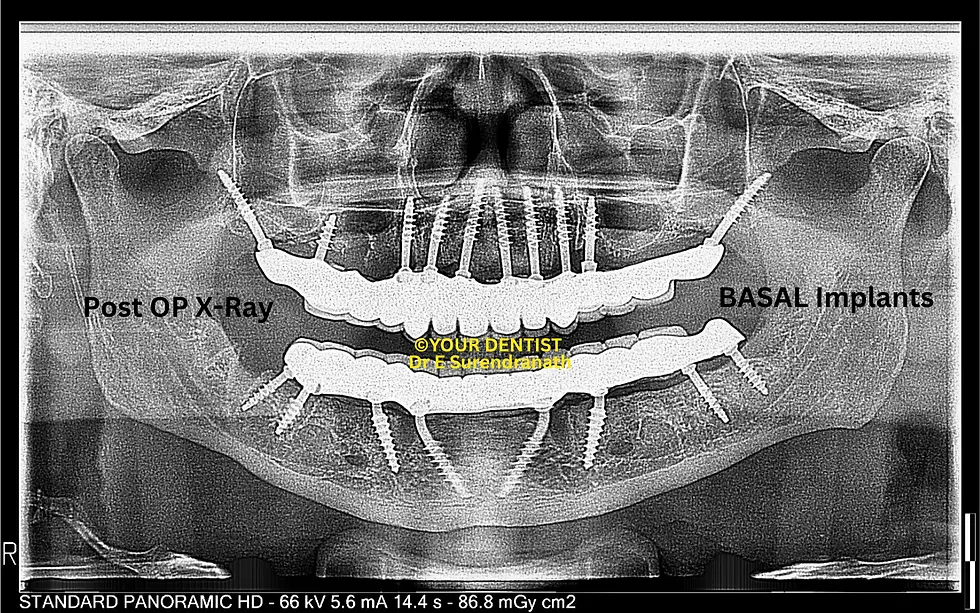

the speciality if your dentist dental hospital is that we not only deal with normal all on 4 and all on 6 but also deal with patients who has less bone or no bone at all...so many people who are rejected for implants elsewhere can come to us for advanced implant options for highly resorbed jaw bones like PATZI protocol or all on 6 with zygomas or quad zygomas and many more options like basal, screw retained basal,or compressive multiunit implants and so on...infact we have a record of not rejecting a case even in utmost resorbtion cases we even opt for patient specific implants.

At YOUR DENTIST Vijayawada, full mouth implant solutions are customized using techniques such as All-on-4, All-on-6, zygomatic implants or pterygoid implants (if needed), or basal implants, or advanced combinations, depending on bone condition.